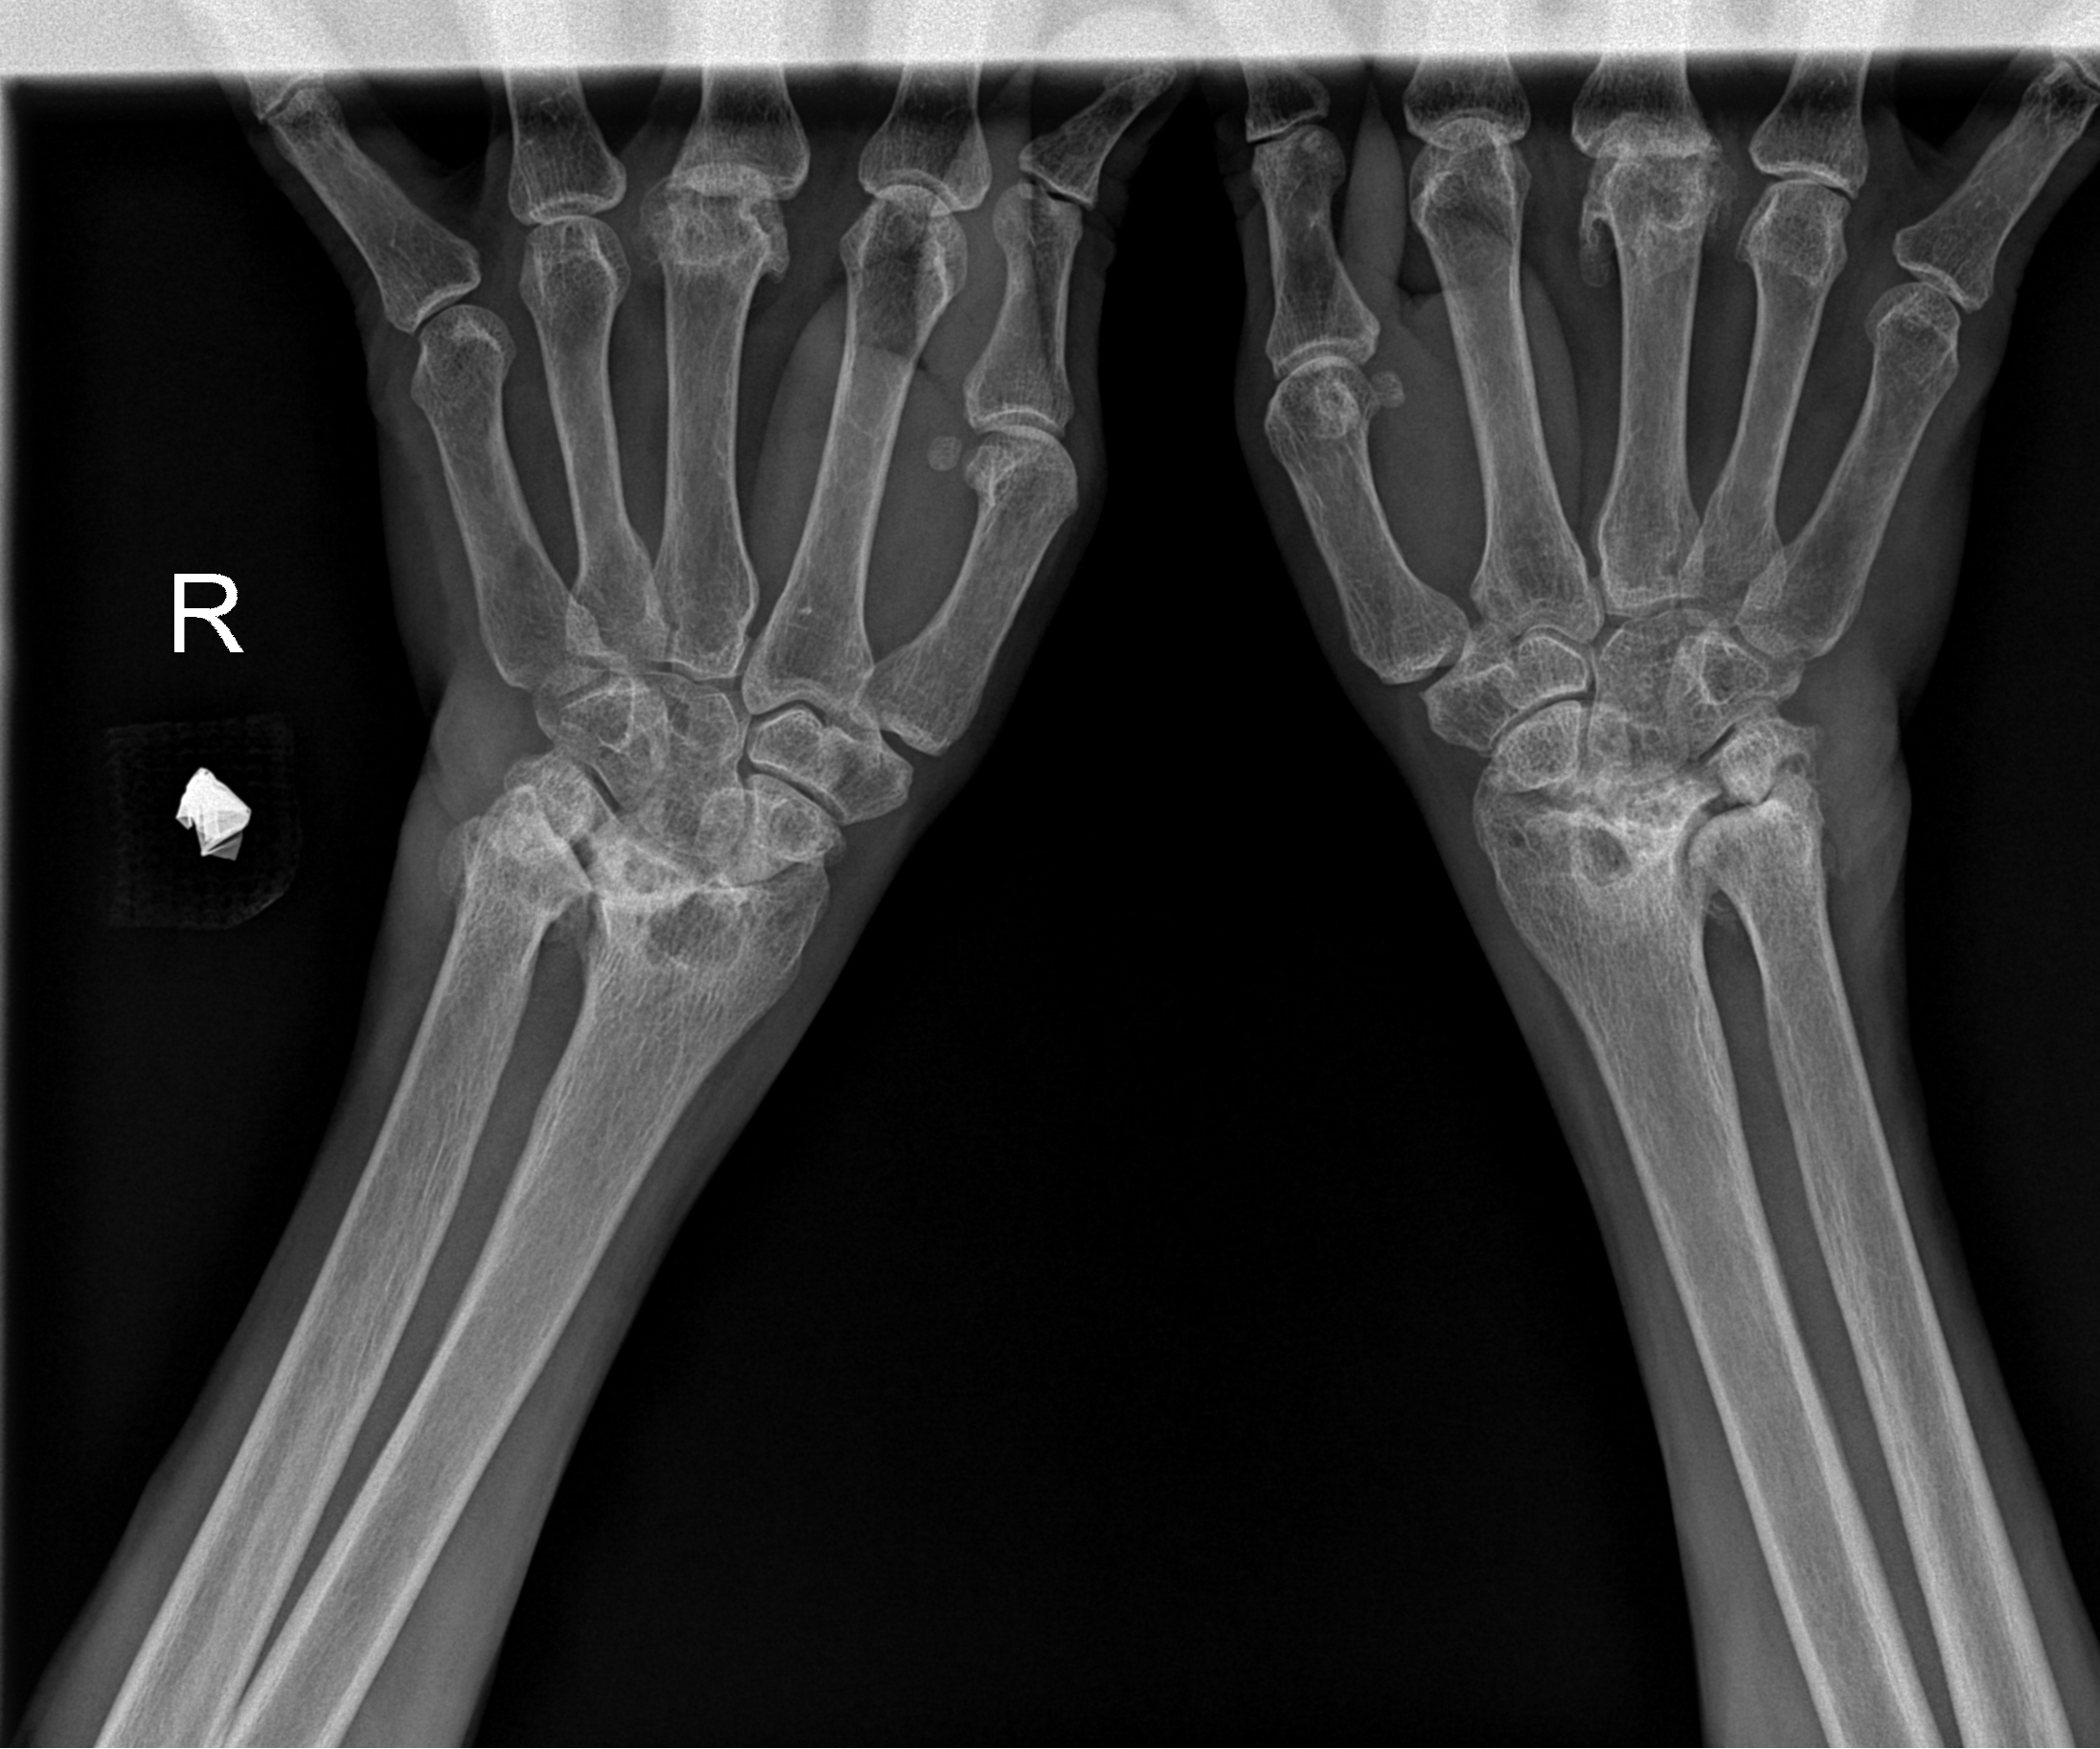

Carpal tunnel syndrome can cause pain, numbness, tingling, and weakness in the hand and wrist, often making everyday tasks like typing, gripping, or lifting difficult.

If non-surgical treatments such as wrist splints, lifestyle changes, or steroid injections don’t relieve your symptoms, your consultant may recommend carpal tunnel surgery.